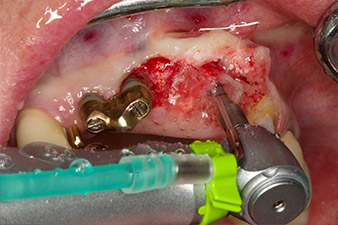

Después de la cicatrización primaria, los tejidos blandos se modelaron con ayuda del puente con base reconstruida. Dos meses después, se procedió a la exposición del área con una incisión de la cresta maxilar en sentido ligeramente palatino (figura 2).

El hueso alveolar de la posición 22 resultó tener unas dimensiones suficientes. Las figuras 2 y 4 muestran la preparación del lecho del implante, el corte de rosca y la colocación del implante con el equipo Implantmed.